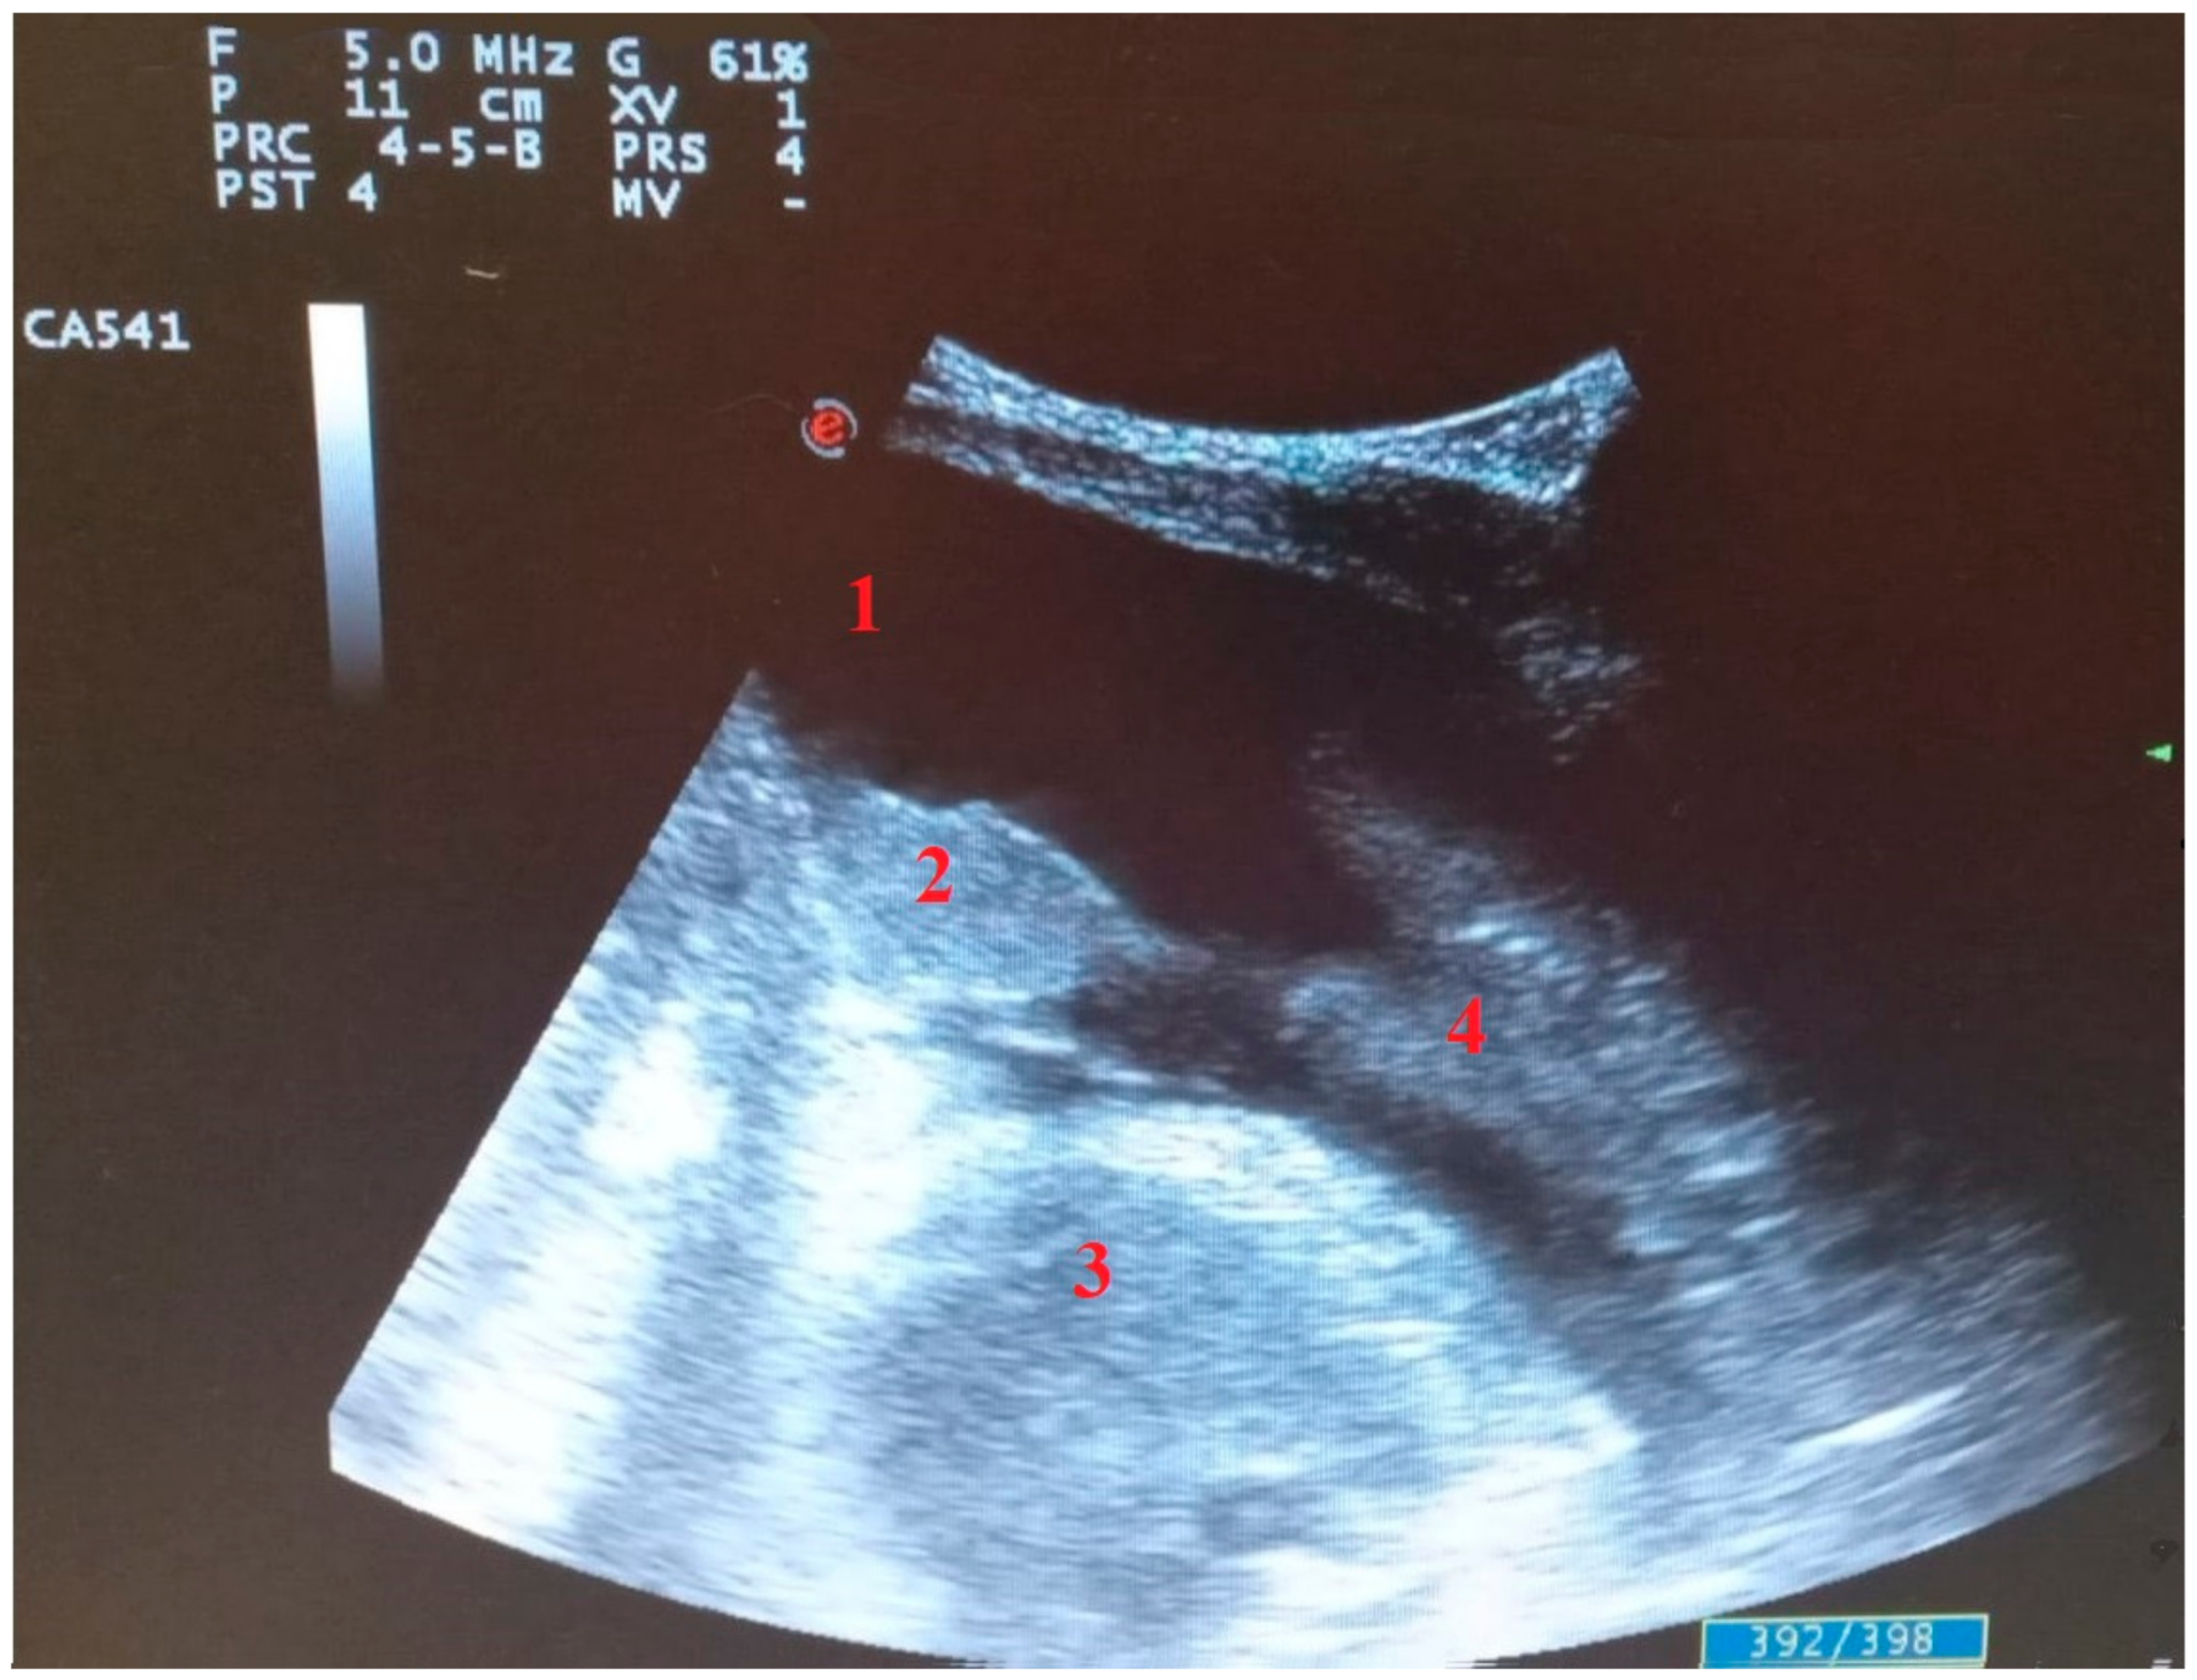

3. Lung Ultrasound in COVID-19 Pneumonia: Findings